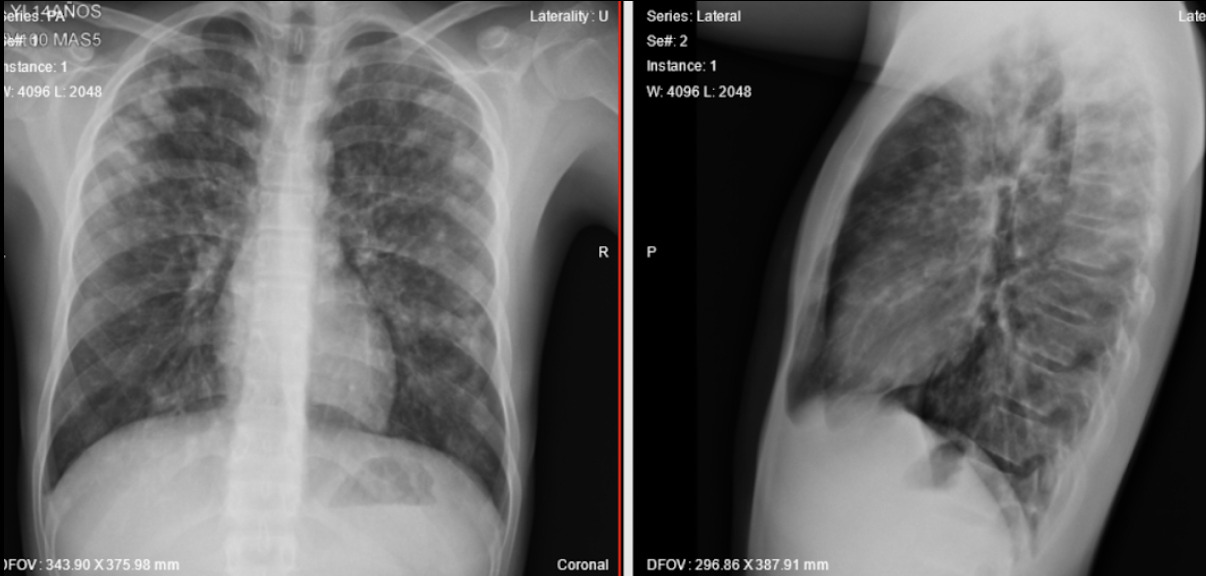

En un principio, en el servicio de urgencias, se inició administración de oxígeno suplementario a bajo flujo a través de cánula nasal a 1 l/min, y líquidos endovenosos con lactato de Ringer para administración aproximada de 60 cm3 cada hora y tres inhalaciones de salbutamol. Después de la valoración por el servicio de Pediatría y el diagnóstico de EPA se suspendió la administración de líquidos endovenosos e iniciar furosemida a 20 miligramos por vía intravenosa, cada 12 horas, durante los 3 días de hospitalización del paciente. Se realizó el seguimiento de respuesta medicamentosa con la clínica del paciente y radiografía de tórax diaria (Ver figura 2). La cronología del caso se describe en la tabla 1.

Figura 2. Exploración radiológica tras un día de intervención.

Se valora al paciente nuevamente quien refiere mejoría en síntomas respiratorios, sin nuevos episodios eméticos. Durante el día se solicita nueva radiografía de tórax anteroposterior y lateral para evaluar evolución clínica donde se evidencia notable disminución de infiltrados algodonosos generalizados por lo que se decide continuar con el manejo médico instaurado y estricta vigilancia respiratoria.